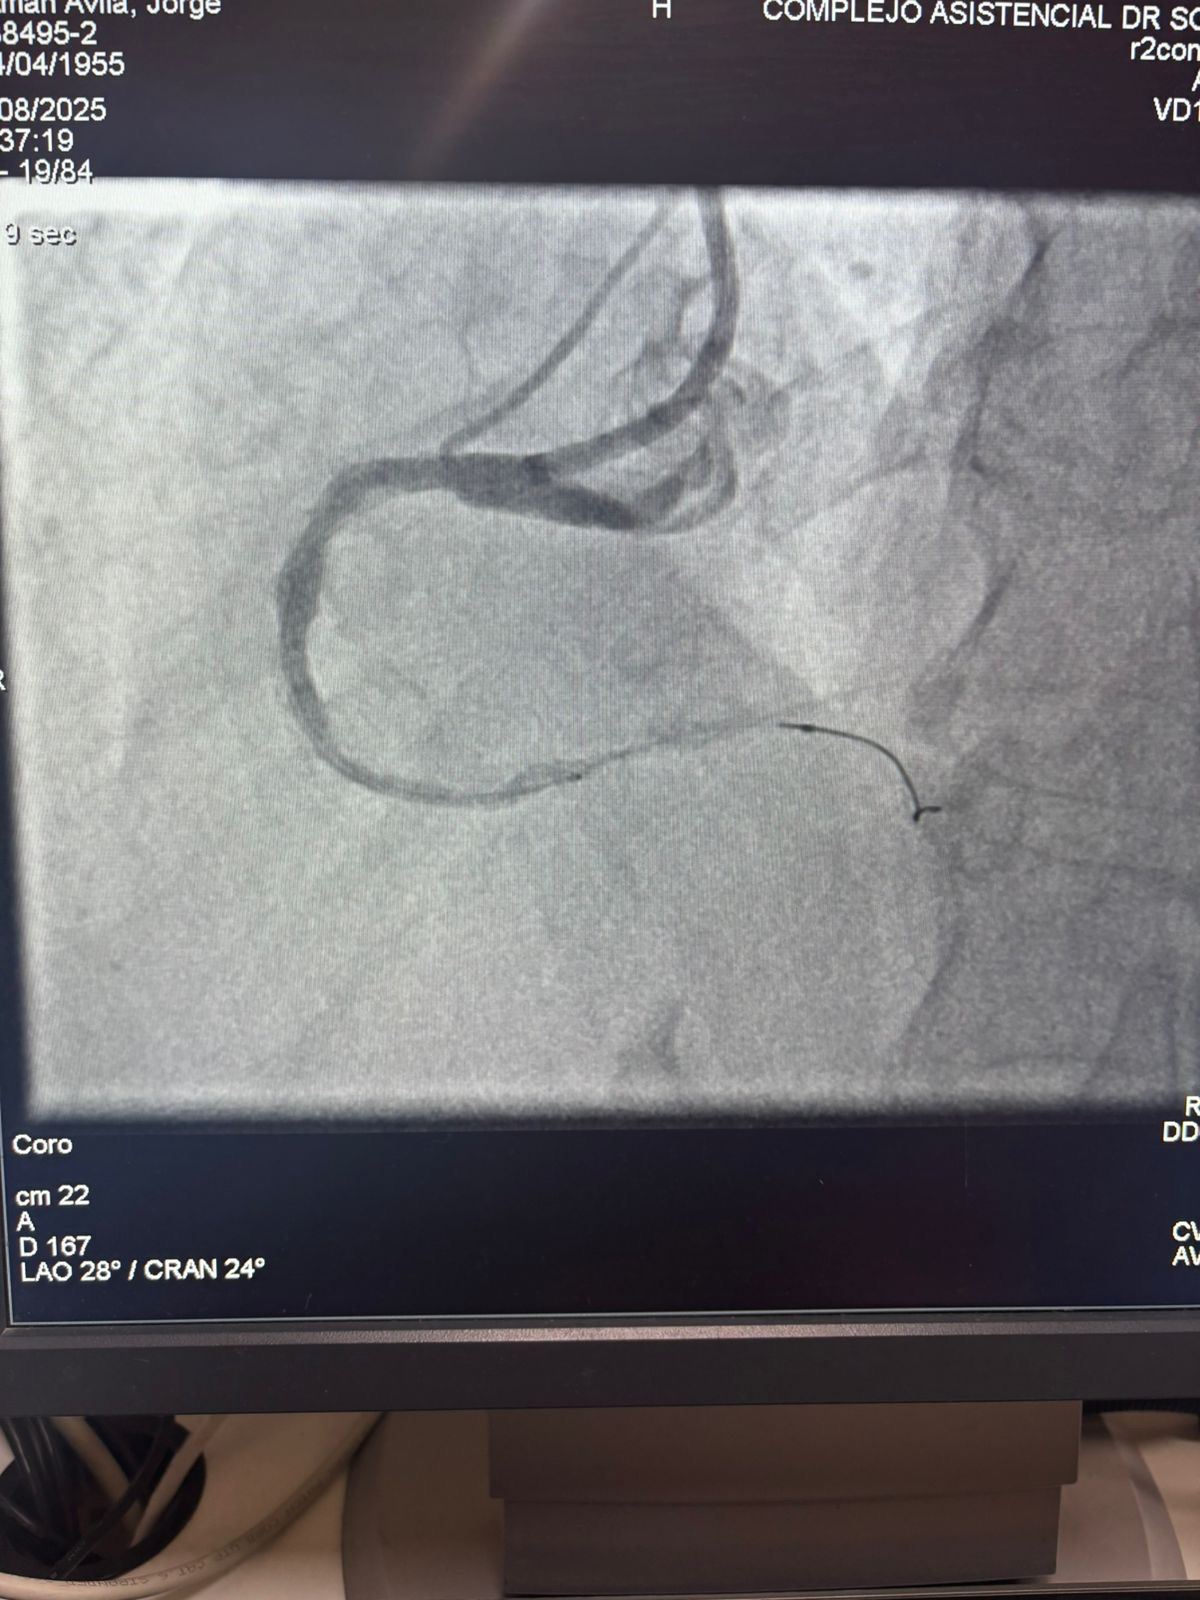

Мы гордимся тем, что поделились замечательным случаем из больницы Sótero del Río, Чили, где доктор Мартин Вальдебенито успешно вылечил сильно кальцинированное поражение в правой коронарной артерии (первая кривая), используя нашу систему катетера с расширенным баллоном IVL.

Процедура достигла выдающихся результатов, при этом кальцинированная область эффективно треснулась и поток сосудов восстановился. Это является еще одной вехой в расширении глобального доступа к передовым решениям для сложной коронарной кальцификации.

Сравнение между предварительными и послепроцедурными ангиографическими изображениями ясно демонстрирует значительное клиническое влияние нашей технологии IVL.